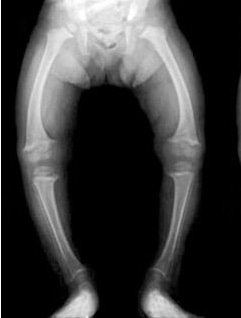

Переднезадние рентгенограммы обеих нижних конечностей в положении стоя помогают отличить физиологическую О-образную деформацию от патологической У этого пациента с Х-сцепленным гипофосфатемическим рахитом (XLH) отмечаются множественные расширенные зоны роста. В метафизах видна остеопения, сам метафиз расширен. Искривление обычно более диффузное по всей кости, а не локализуется в области проксимальной большеберцовой кости.

Рентгенологические признаки:

Снижение плотности костной ткани

Расширение и "чашеобразная" деформация ростковых зон

Расширенные метафизы

Псевдопереломы (зоны Лоозера)

Деформации длинных костей